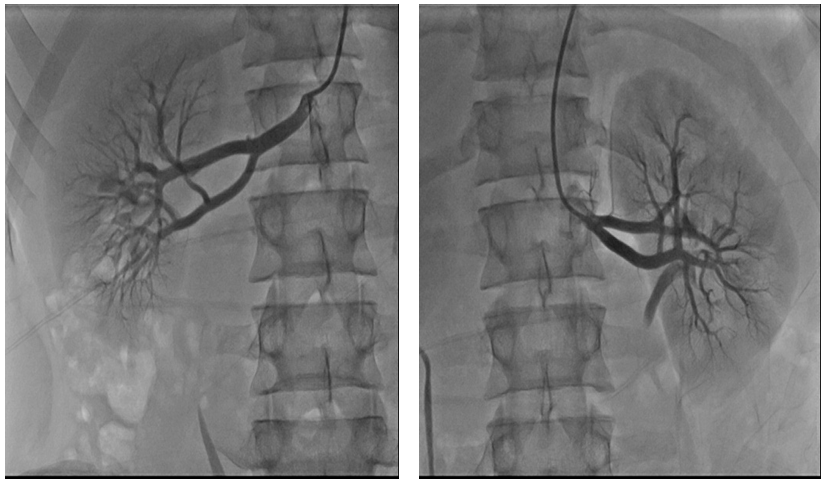

Echocardiography showed normal left ventricular dimension with moderate left ventricular hypertrophy, IVS-13mm, ZZ -11mm, and the high pressure gradient (56mmHg) by Doppler echocardiography at the across stenotic segment. This finding make a suspicion of coarctation of aorta and we done aortography (Figure 4) which confirm the diagnosis of juxtaductal coarctation. The renal angiography (Figure 5) was normal. The computed tomography (KT) aorta (Figure 6) showed juxtaductal coarctationwith high stenosis 77%-80% and prominent a.mamaria internal with collateral vessels across inferior epigastric, intercostal and scapular artery.

Figure 4: Aortography with juctaductal coarctatio.

Figure 5: Normal renal angiography.